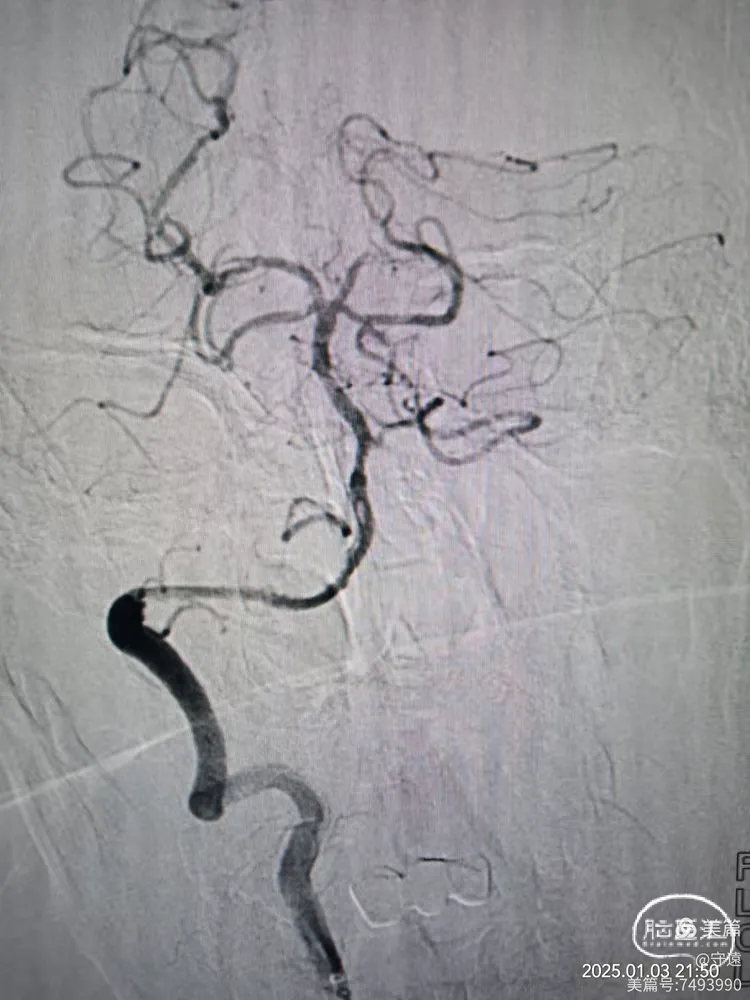

回撤导管至V3段造影,狭窄不明显,血流通畅。

回撤至椎动脉起始段造影血流通畅,左侧大脑后似有少量血栓逃逸,推注替罗非班10mL,结束手术。